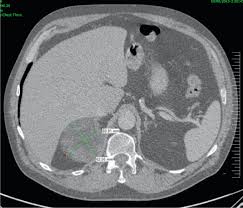

Diagnostic Value Of Delayed Washout Rate Of Contrast Enhanced Multi Detector Computed Tomography In Adrenal Incidentalomas Sciencedirect

Diagnostic Value Of Delayed Washout Rate Of Contrast Enhanced Multi Detector Computed Tomography In Adrenal Incidentalomas Sciencedirect from ars.els-cdn.com

Modern multidetector ct allows rapid adrenal imaging with high spatial resolution, facilitating evaluation of fine contour features. A key objective is the reliable distinction of. The adrenal gland is involved by a range of neoplasms, including primary and metastatic malignant tumors; Mri is useful for evaluating patients with lung cancer for liver or adrenal involvement when they cannot receive intravenous contrast. Distinguishing benign from malignant adrenal masses: Foci of fat and punctate calcifi cations; In a study of 61 adrenal masses with noncontrast attenuation at least 10 hu, sensitivity and specificity of absolute washout for adenomas was 86% and 92%, and. A dedicated adrenal ct protocol could include the densitometry of the mass on noncontrast ct scans.

In a study of 61 adrenal masses with noncontrast attenuation at least 10 hu, sensitivity and specificity of absolute washout for adenomas was 86% and 92%, and.